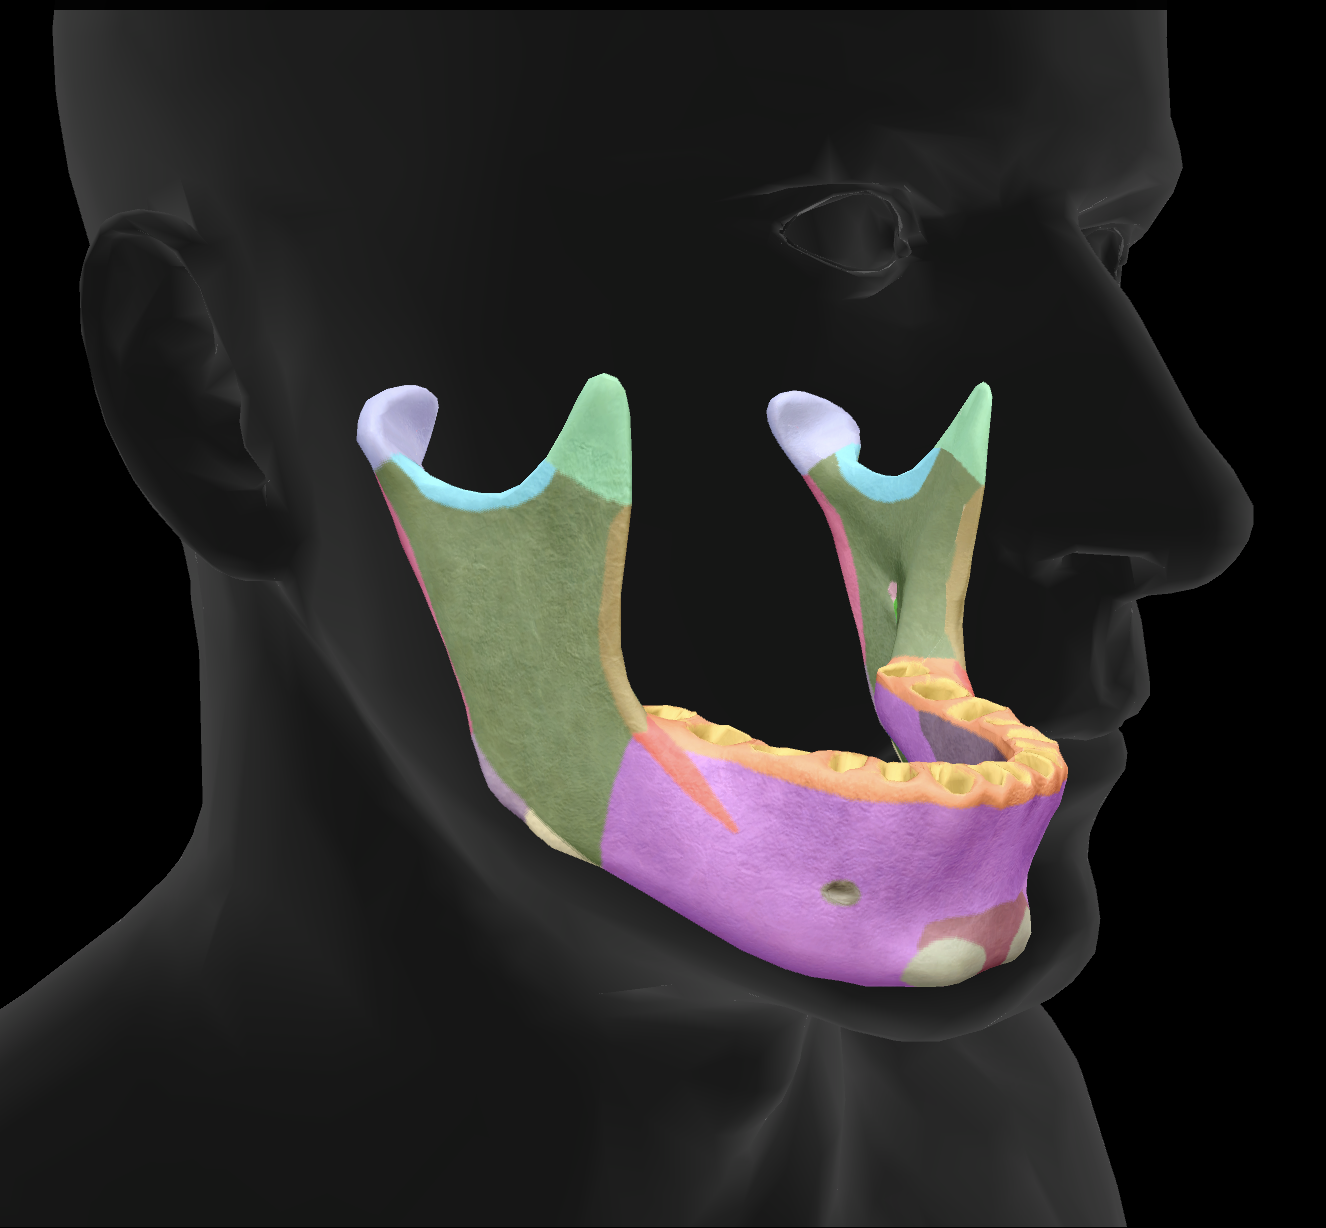

What bone is this?

mandible

What is the name of this feature?

mental foramen

What is the name of this feature?

mandibular condyles

What is the name of this feature?

ramus

What is the name of this feature?

alveolar process

What is the name of this feature?

mandibular notch

What is the name of this feature?

angle

What is the name of this feature?

body

What is the name of this feature?

coronoid process

What is the name of this feature?

mental protuberance